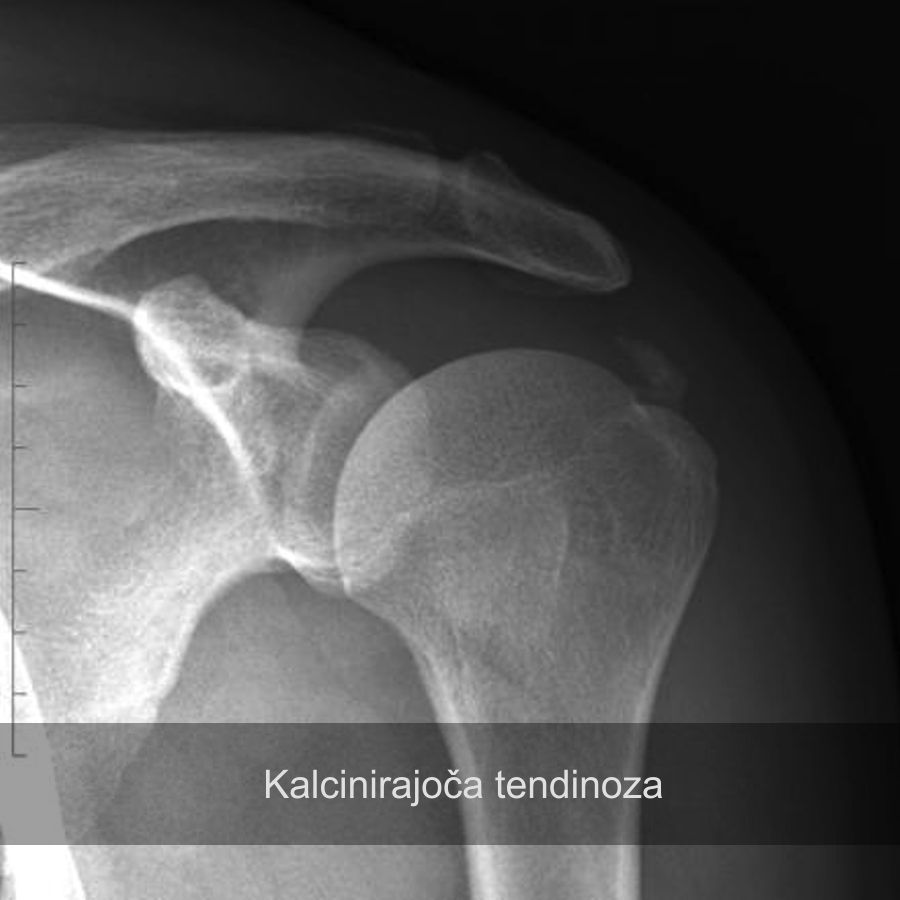

kalcinacije, rama, bolečina v rami

Kalcinati v ramenu

Konzervativna terapija, artroskopija rame